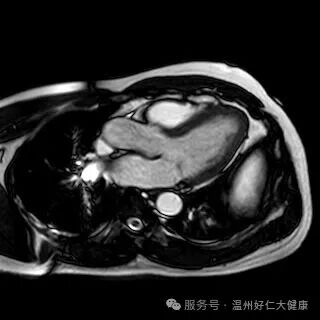

针对心脑血管早筛的核心需求,我院全力推进冠脉磁共振检查技术普及,凭借无创、无辐射、不打造影剂的硬核优势,攻克传统筛查的痛点,成为不同人群冠脉血管筛查的优选方案,让早期血管病变无所遁形:无创安全,适配全人群:全程无需插管、不注射造影剂,从根源规避造影剂过敏、肾脏代谢负担等问题,肾功能不全、备孕、造影剂过敏等特殊人群也能安心检查,真正实现 “零负担筛查”; 零辐射高精准,捕捉隐匿病变,无任何电离辐射,即使多次复查也不会对身体造成损伤;成像精度可清晰识别冠脉血管软斑、硬斑等斑块性质,精准判断血管狭窄程度,哪怕是早期隐匿的微小病变,也能精准检出; 一站式筛查,兼顾血管与心脏:不仅能排查冠脉血管病变,还能同步评估心肌灌注、心脏收缩舒张功能,清晰呈现心肌细微结构,一站式完成 “血管 + 心脏” 全面检查,为冠心病早期筛查、高危人群动态监测提供精准的诊断依据。